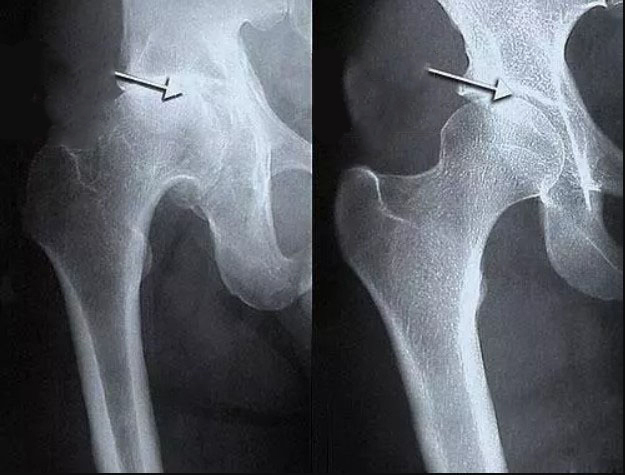

- Los osteofitos son sales calcificadas responsables del 97% de las demás enfermedades articulares y de la columna, como la artritis, artrosis, osteocondrosis, osteoporosis, reumatismo, bursitis e incluso quistes sinoviales.

Estas sales, al depositarse en la superficie de la articulación, actúan como papel de lija, dañando los tejidos circundantes, los huesos y el cartílago. A medida que los cristales crecen, comienzan a dañar los tejidos musculares, los tendones, los vasos sanguíneos y los capilares, provocando inflamación, infección, hinchazón y dolor intenso.

En los casos avanzados, grandes acumulaciones de estas sales pueden romper fácilmente una parte del hueso con un movimiento brusco, lo que lleva a una discapacidad total e inmovilidad permanente de la articulación.

Es un error muy peligroso pensar que el calcio es beneficioso para las articulaciones. Sí, el calcio es útil, pero solo para las articulaciones sanas. Cuando las articulaciones ya duelen o crujen, eso significa que ya se ha formado una capa de osteofitos, y el calcio, además de fortalecer el tejido óseo, también fortalece estos osteofitos salinos, empeorando y acelerando su crecimiento.